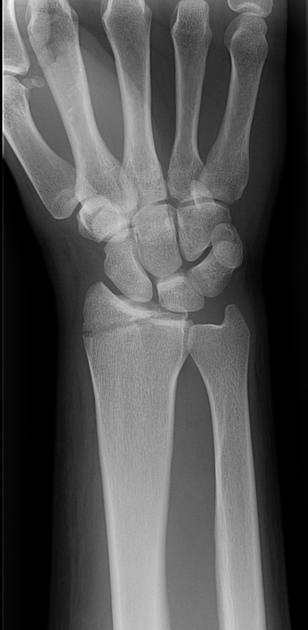

Describe Barton fracture?

A

DORSAL BARTON = usual

- Oblique intraarticular fracture of the dorsal rim of the distal radius with displacement of the carpus along with the fracture fragment

- Results from high-velocity impact across the articular surface of the radiocarpal joint, with the wrist in dorsiflexion at the moment of impact

VOLAR /REVERSE BARTON = rarer

- Wedge-shaped articular fragment sheared off the volar surface of the radius (volar rim fracture), displaced volarly along with the carpus

- Wrist in volar flexion at time of injury; also referred to as reverse Barton’s fracture; much rarer than dorsal Barton fracture